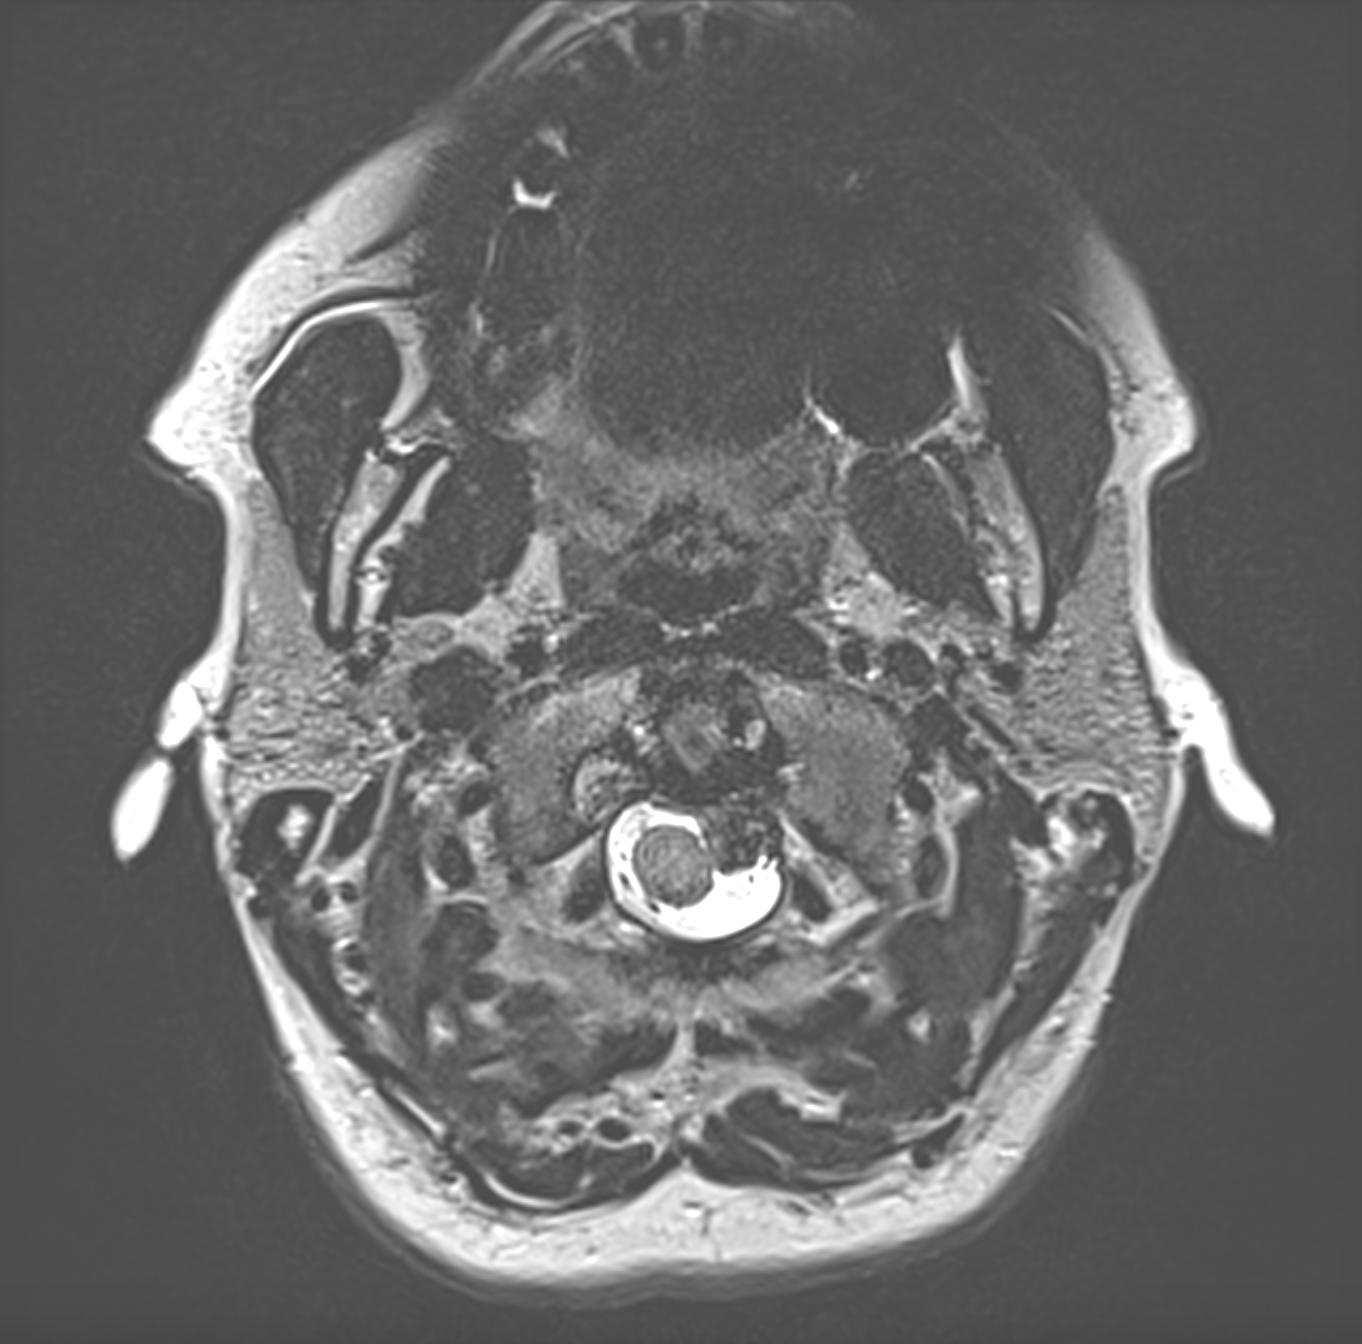

În final, am reușit să rezecăm tumora în totalitate, rămânând doar baza ei de inserție pe dura mater, care a fost minuțios coagulată, pentru a distruge ultimele resturi de celule tumorale. Pacienta a evoluat foarte bine, acuzând doar dureri locale moderate si un grad de pareză de nervi cranieni XI (mușchiul trapez stâng, care s-au recuperat in cea mai mare parte sub kinetoterapie) și XII (jumătatea stângă a limbii, fără impact de durată asupra vorbirii sau a masticației). Întotdeauna efectuăm un RMN cerebral de control a doua zi după operație, care, in cazul de față, a arătat absența complicațiilor postoperatorii sau a oricărui reziduu tumoral, fapt confirmat și prin RMN cerebral de control la 6 luni. Diagnosticul histopatologic a fost de asemenea favorabil – meningiom grad I, tumora benignă, fără risc de malignizare. Vom mai urmări pacienta prin RMN cerebral periodic dar putem considera că operația a fost un succes iar pacienta vindecată. Dată fiind localizarea acestor tumori, la joncțiunea trunchiului cerebral cu măduva spinării, tratamentul chirurgical este deosebit de provocator și, de multe ori, grevat de complicații majore. La spitalul Nord beneficiem însă de o experiență vastă neurochirurgicală, neurologică, anestezică și radiologică, precum și de ultimele modele de aparatură și instrumentar chirurgical, astfel incât putem aborda în deplină siguranță chiar și cele mai dificile cazuri neurochirurgicale.